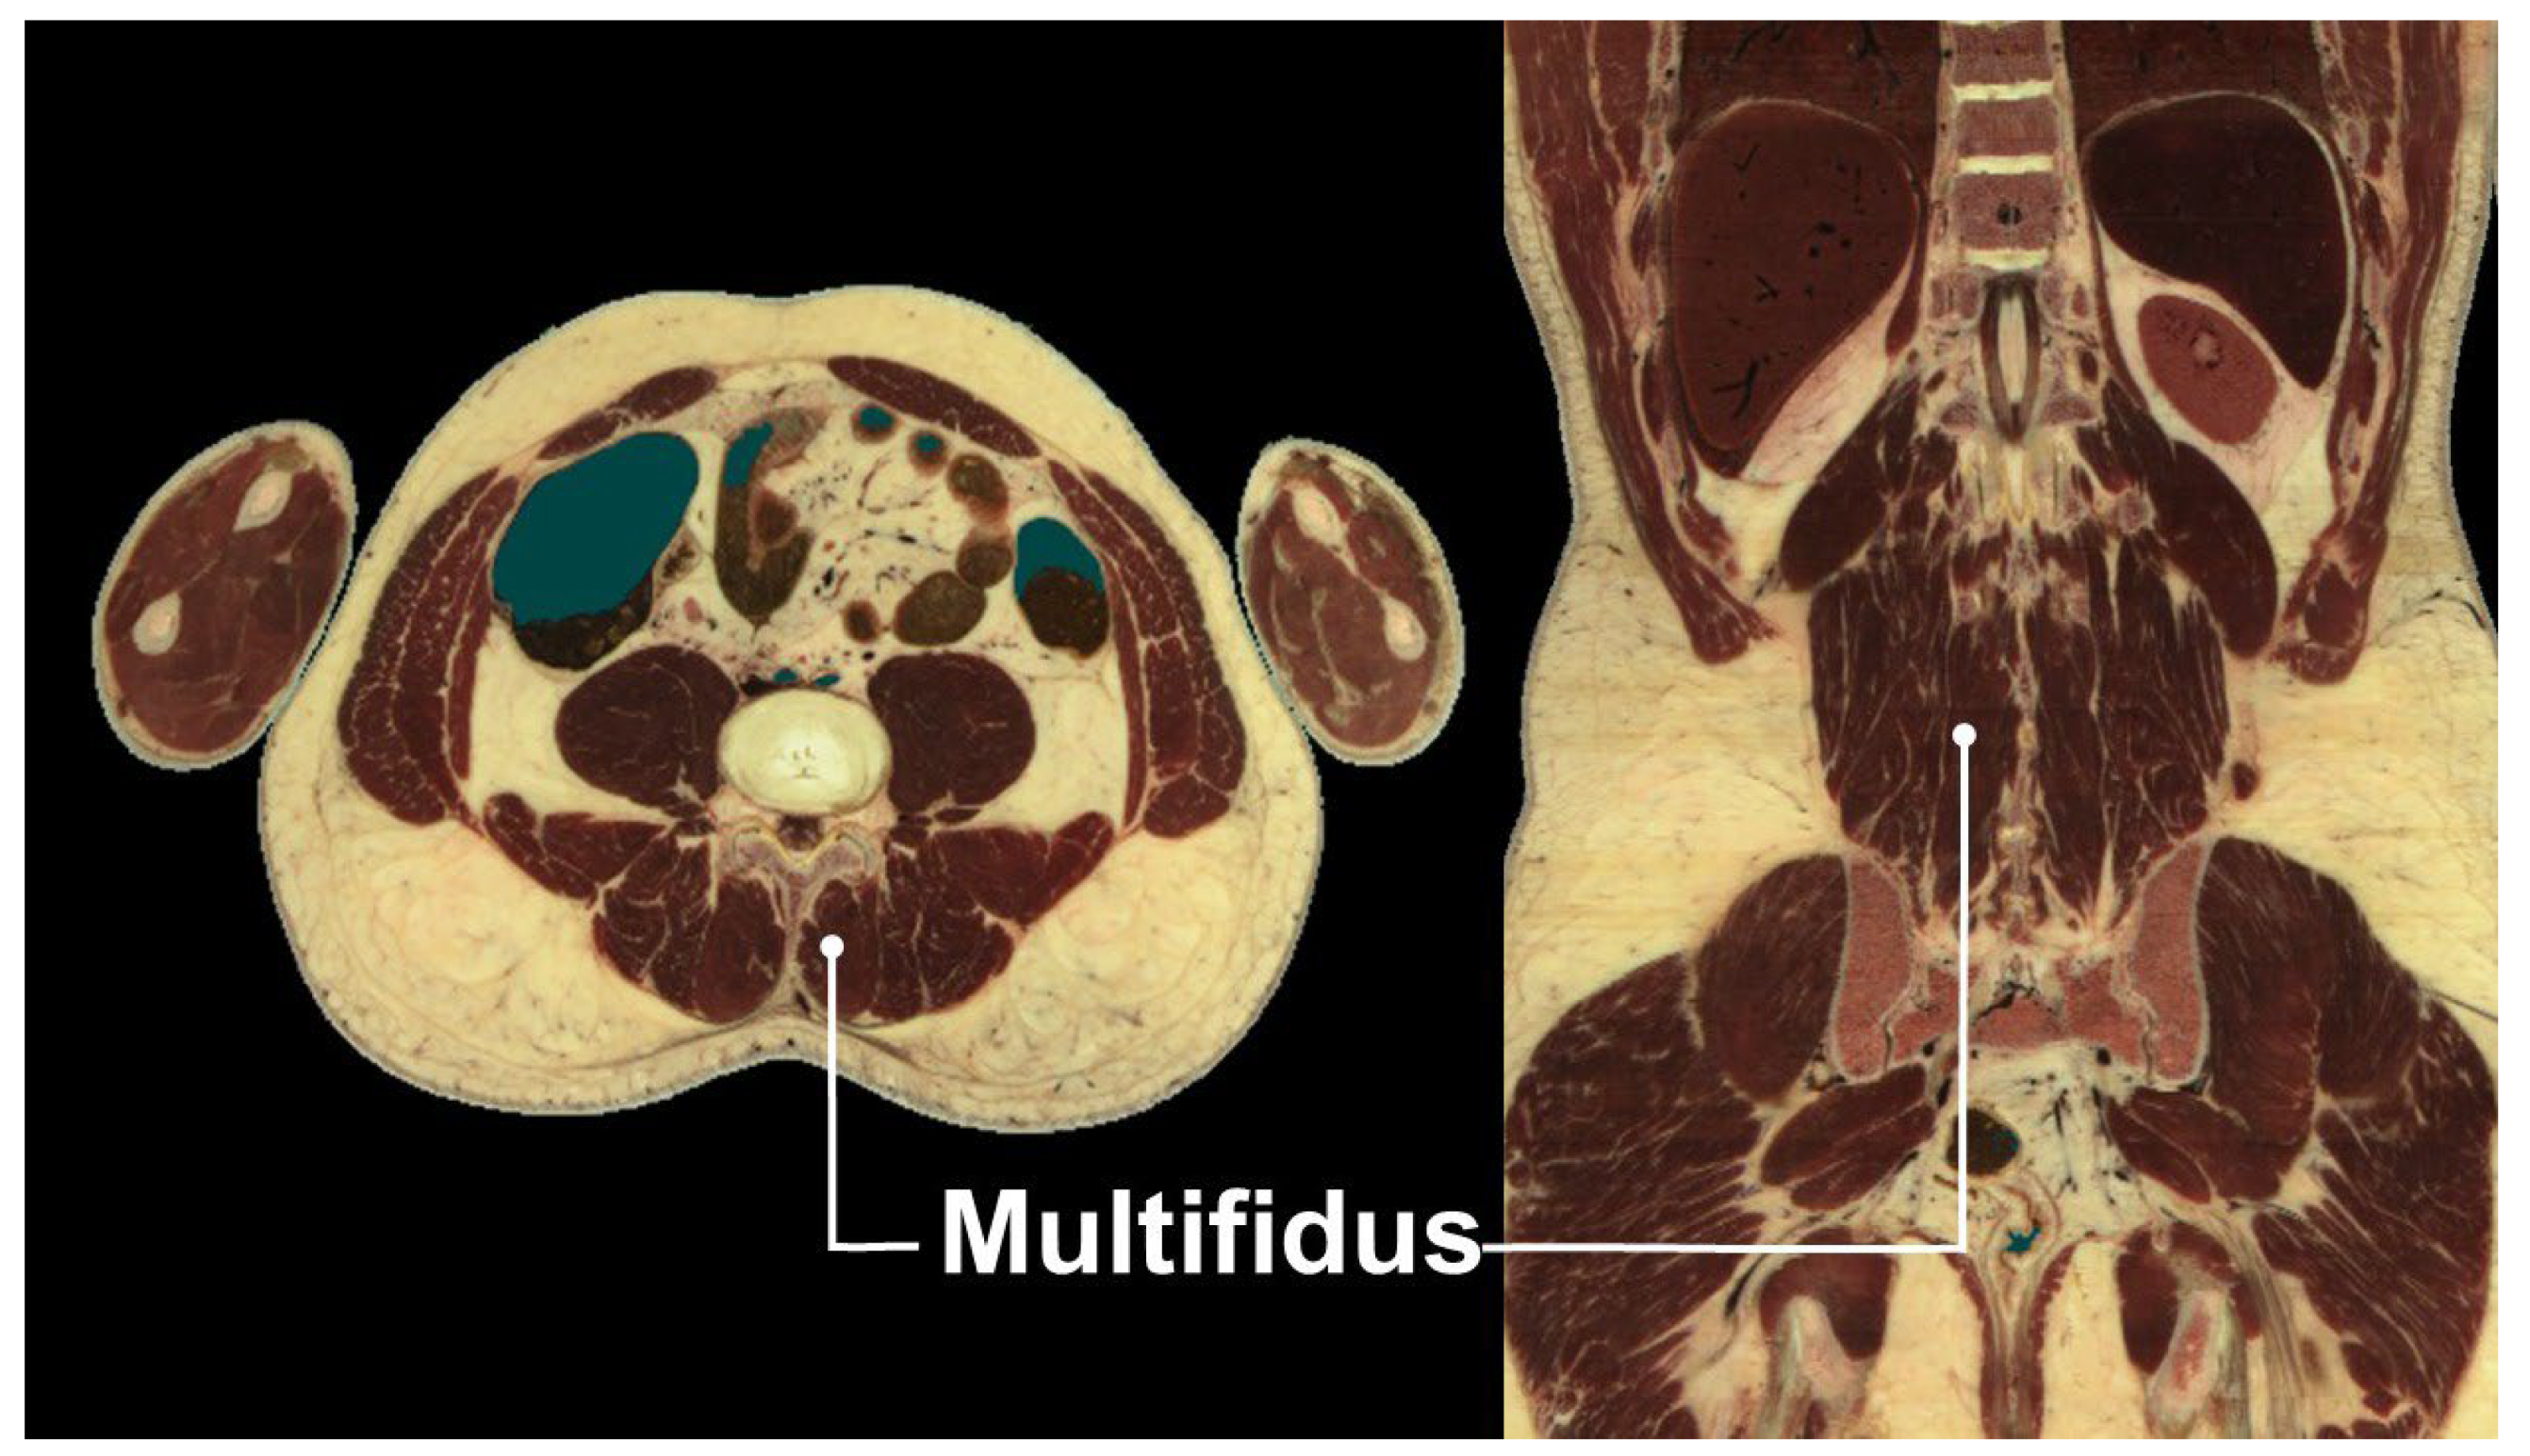

4. Multifidus Muscle and Low Back Pain

- Macintosh, J.E.; Valencia, F.; Bogduk, N.; Munro, R.R. The morphology of the human lumbar multifidus. Clin. Biomech. 1986, 1, 196–204. [Google Scholar] [CrossRef]

- Freeman, M.D.; Woodham, M.A.; Woodham, A.W. The role of the lumbar multifidus in chronic low back pain: A review. PM R 2010, 2, 142–146. [Google Scholar] [CrossRef]

- Hung, C.Y.; Wang, B.; Chang, H.C.; Wu, W.T.; Liu, P.T.; Chang, K.V.; Su, D.C.; Mezian, K.; Ricci, V.; Özçakar, L. Pictorial Essay on Ultrasound and Magnetic Resonance Imaging of Paraspinal Muscles for Myofascial Pain Syndrome. Life 2024, 14, 499. [Google Scholar] [CrossRef]